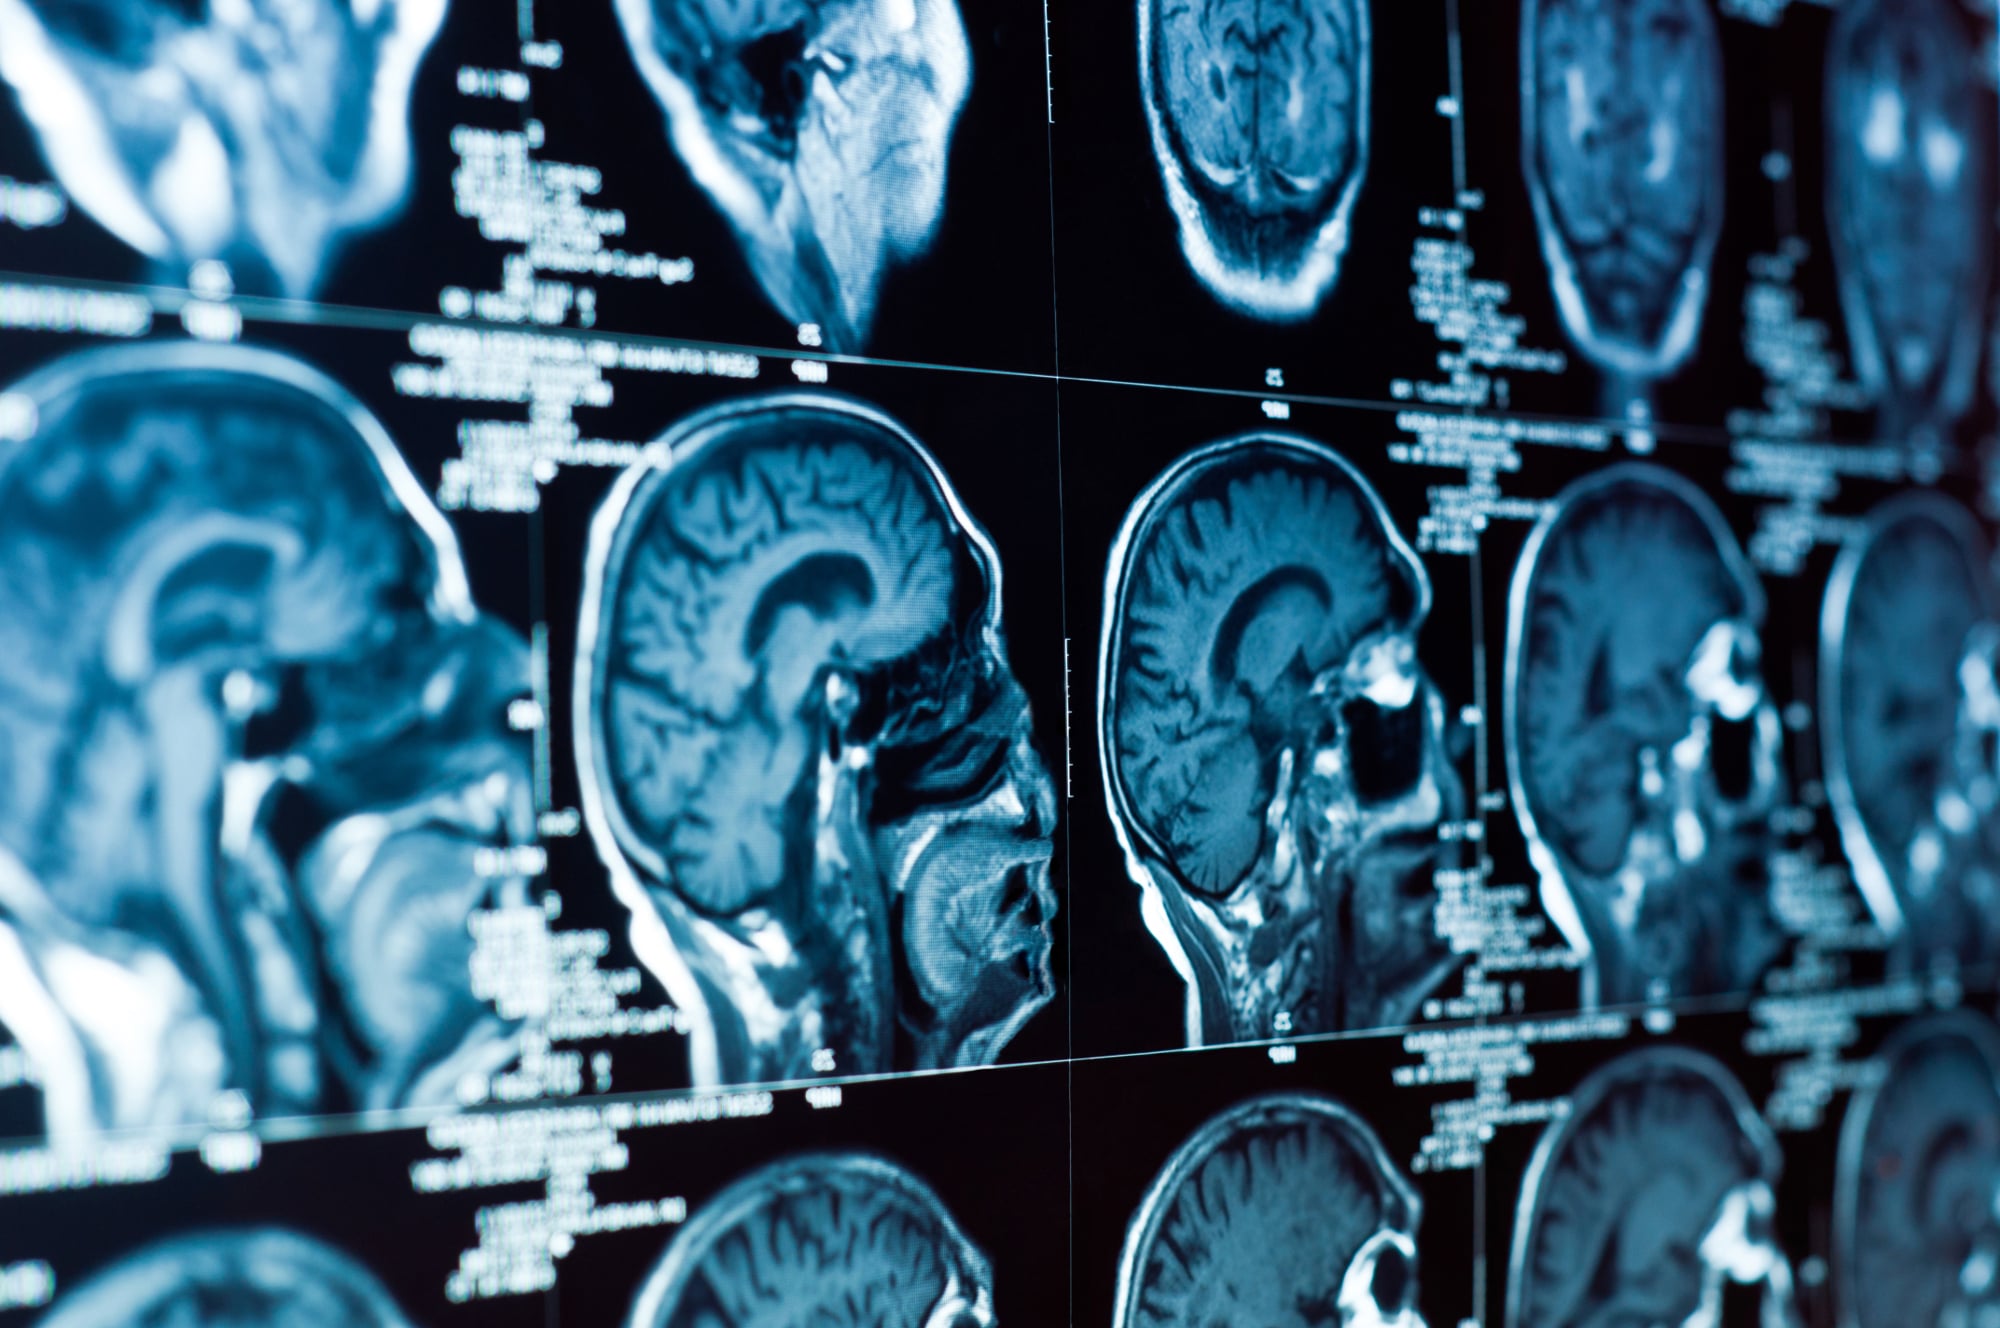

Анатомия мозга: Рентгеновские снимки для презентаций